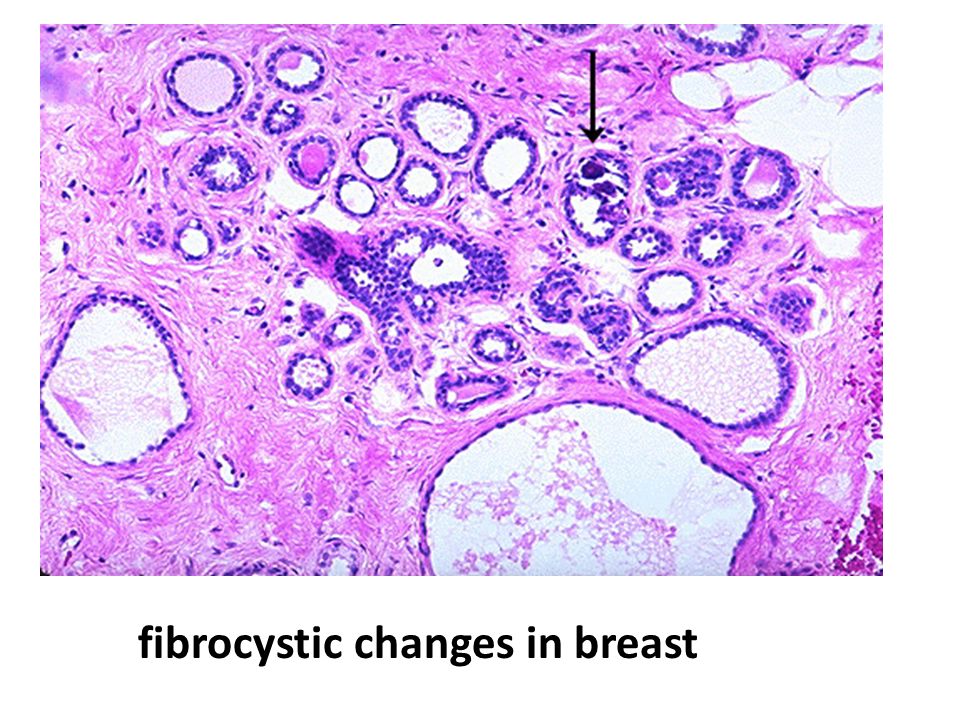

Исследование: микропрепарат молочной железы в медицине

Раздел: Снимки-откровения